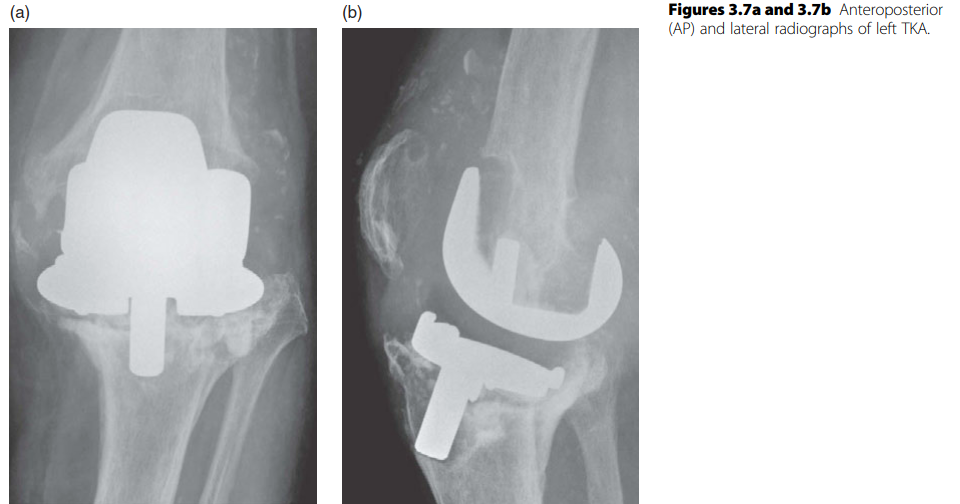

KNEE Structured oral examination question7: Revision knee replacement EXAMINER : Have a look at these images …